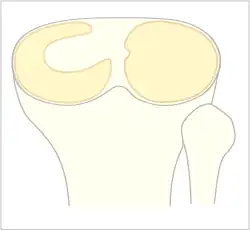

The Watanabe classification of discoid lateral meniscus is: (A) Incomplete, (B) Complete, and (C) Wrisberg-ligament variant[1]

Normally, the meniscus is a thin crescent-shaped piece of cartilage that lies between the weight bearing joint surfaces of the femur and the tibia. It is attached to the lining of the knee joint along its periphery and serves to absorb about a third of the impact load that the joint cartilage surface sees and also provides some degree of stabilization for the knee. There are two menisci in the knee joint, with one on the outside (away from midline) being the lateral meniscus and the inner one (towards midline) the medial meniscus. A discoid meniscus is a congenital anomaly of the knee found in 3% of the population (up to 15% in Asia). It typically affects the lateral meniscus and may be found bilaterally (20%). Instead of the narrow crescent shape, as seen in a normal meniscus above, a discoid meniscus is thickened, and has a fuller crescent shape. In addition, a discoid meniscus does not taper as much towards the center of the joint and is shaped like a disc. The thickness of the meniscus, its diminished vascular blood supply, and in some instances, weak capsular attachment, makes it more prone to tears compared to a normal meniscus. The anomaly in itself is asymptomatic; however, a tear of the meniscus can result in pain, swelling, and snapping in the affected knee. The orthopedic classification of discoid menisci includes: complete, incomplete or Wrisberg-ligament types as depicted here. Coverage of the lateral tibial plateau determines the designation of complete or incomplete. The Wrisberg-ligament type has an abnormal posterior attachment by attaching to part of the posterior cruciate ligament.